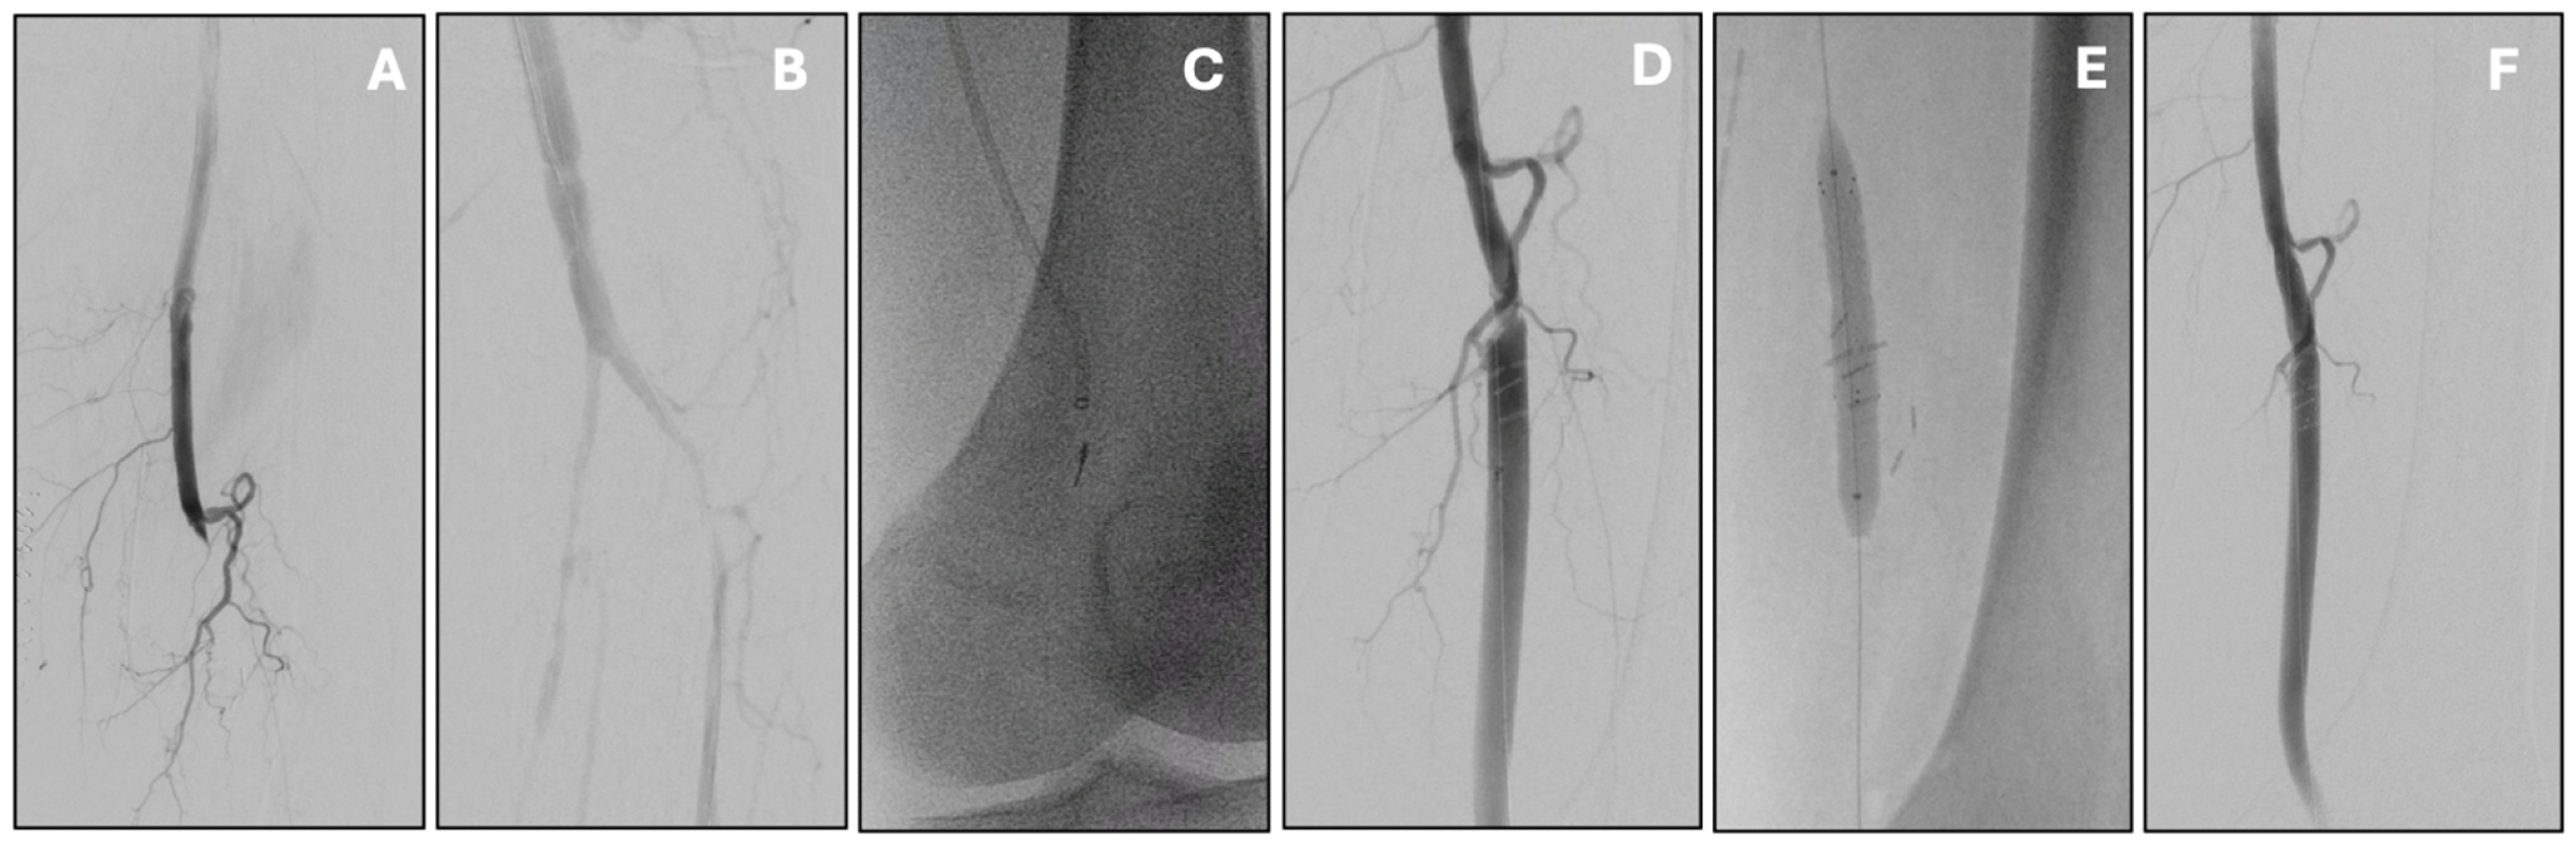

Figure 2. Acute infrainguinal bypass occlusion managed by percutaneous mechanical thrombectomy with the Indigo Penumbra system. Initial angiography showed popliteal graft thrombosis (A) with distal re-opacification of the popliteal artery (B). Mechanical thrombectomy was carried out with multiple passes of the Indigo Penumbra system (C), resulting in effective thrombus removal. This also uncovered a proximal anastomotic stenosis (D), which was subsequently treated with stenting (E). Final angiography confirmed good patency of the treated segment without residual stenosis or thrombus (F).